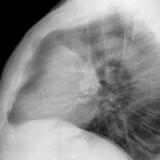

Case 9 Thymoma Lat